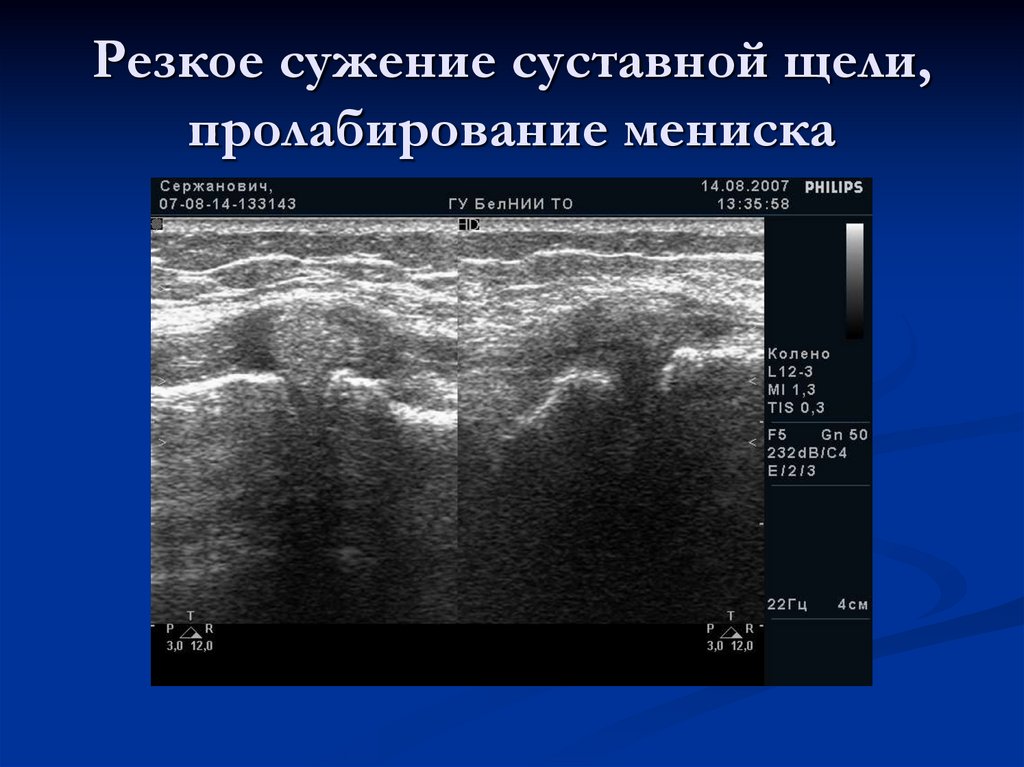

Сужение суставной щели и пролабирование мениска

Резкое сужение суставной щели, пролабирование мениска